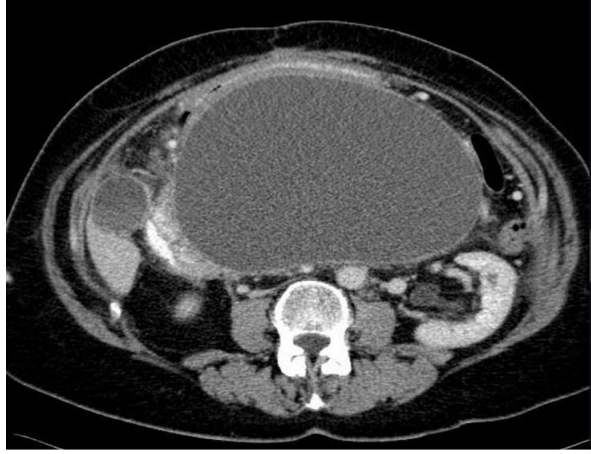

Abdominal Ultrasound: There is an epigastric simple cyst measuring 17x11cm with thickened wall measuring 5.8mm suggesting pancreatic pseudocyst.

Figure 4

FINDINGS: Retro gastric Pancreatic Pseudocyst with a thick wall of 8mm approximately, containing

+- 1.5L of clear and yellowish fluid. The Stomach completely collapsed.

Procedure: Exploratory Laparotomy + “Juracz” Pseudocysto-Gastrostomy. (Trans gastric approach). Sample of the fluid was collected for MCS, Cytology and Amylase)